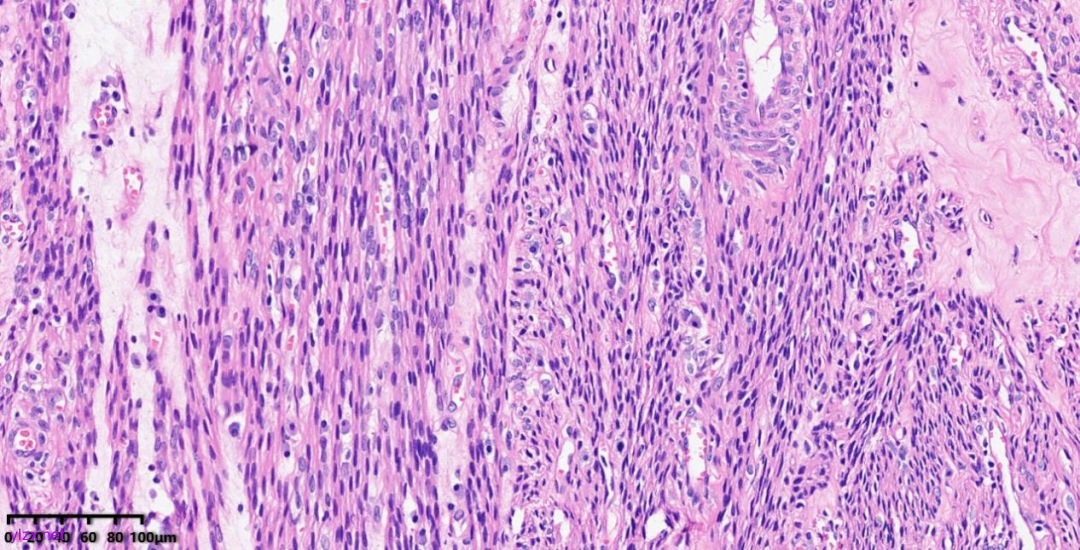

肿瘤细胞以梭形细胞、卵圆形细胞为主,部分为胞浆透亮的上皮样形态,透亮细胞界限较清,胞质淡染或胞浆丰富、嗜酸性,肿瘤内血管丰富,肿瘤细胞围绕血管周围片巢状、束状及放射状排列;肿瘤细胞核异型性不明显,核分裂像少见(<1个/50HPF),染色质开放,可见小核仁;肿瘤间质水肿、黏液变性,纤维胶原增生伴玻璃样变性。

图7~10 高倍镜下:梭形细胞、上皮样细胞组成的巢状、梁状结构,周围包绕纤细的薄壁毛细血管,肿瘤细胞呈放射状排列在血管周围,细胞界限较清,胞浆丰富、嗜酸性或透亮,细胞异型性不明显,核分裂像少见,细胞核呈圆形,染色质开放,可见小核仁;局部少量慢性炎细胞浸润。